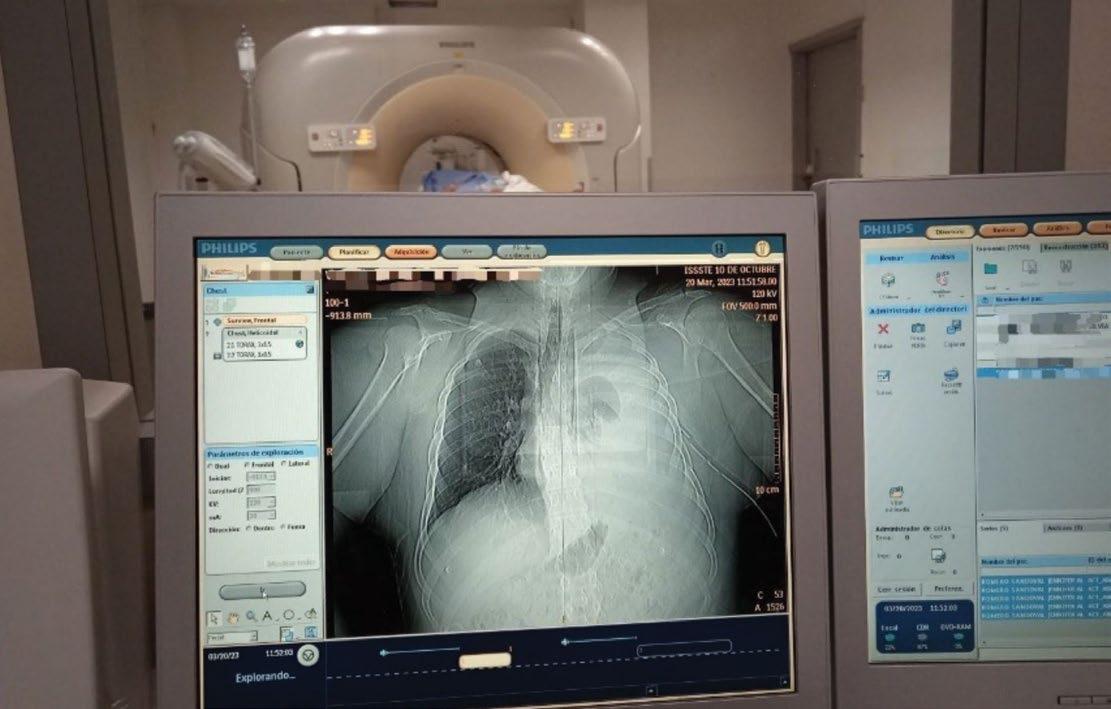

Las imágenes utilizadas en esta obra proceden de diversos archivos particulares e institucionales. Debido a su carácter de difusión y a que no persigue fines lucrativos, las sedes decidieron con plena libertad enviar fotografías para su uso en esta obra.